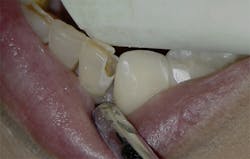

Figure 9: Initial presentation prior to crown lengthening

Figure 10: Immediate post-op hard- and soft-tissue crown lengthening with laser